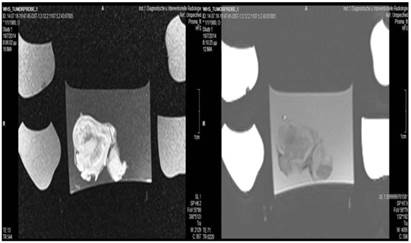

Figure 5

Lipiodol group; T1 sequence: Heterogeneous appearance in the central part of the tumor, low intensity indicates necrosis. T2 sequence: High signal intensity indicates necrosis. White and black arrows indicate lipiodol solution within the tumor. Necrosis is not extensive as presented in the current figures.

Tumor necrosis and apoptosis were the major purposes of our study. Survival was also recorded. Our records and MRI findings indicate that a major toxicity was observed in the group where cisplatin, lipiodol and microwave were applied. None of the animals survived more than a week. Moreover; hemorrhage apart from necrosis was observed inside the tumors. Survival was the following for the groups: microwave (25days) ≥ cisplatin (22 days) > control (20 days) > lipiodol (16 days)> microwave plus lipiodol (16 days) > cisplatin plus lipiodol (12) > cisplatin plus microwave (12 days) > lipiodol plus cisplatin plus microwave (5 days). (Figure 5-12.)